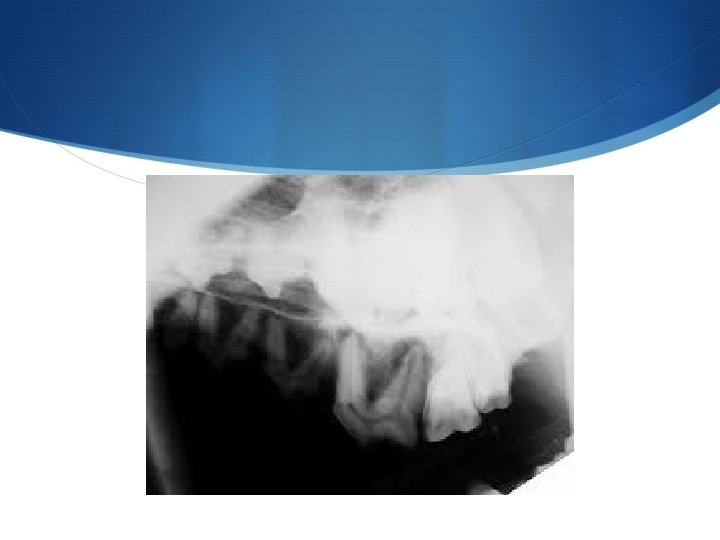

S Esame radiografico Importante per la valutazione di lesioni occupanti spazio delle cavità nasali, si valuta la conservazione dell’architettura della trabecolatura ossea dei turbinati e le eventuali alterazioni. Importante il confronto tra la parte coinvolta e la parte contro laterale sana. E’ importante eseguire sempre entrambe le proiezioni anche se la più importante E DI PIU’ AGEVOLE LETTURA è QUELLA INTRAORALE

S Diagnosi Si basa sui reperti clinici e radiologici